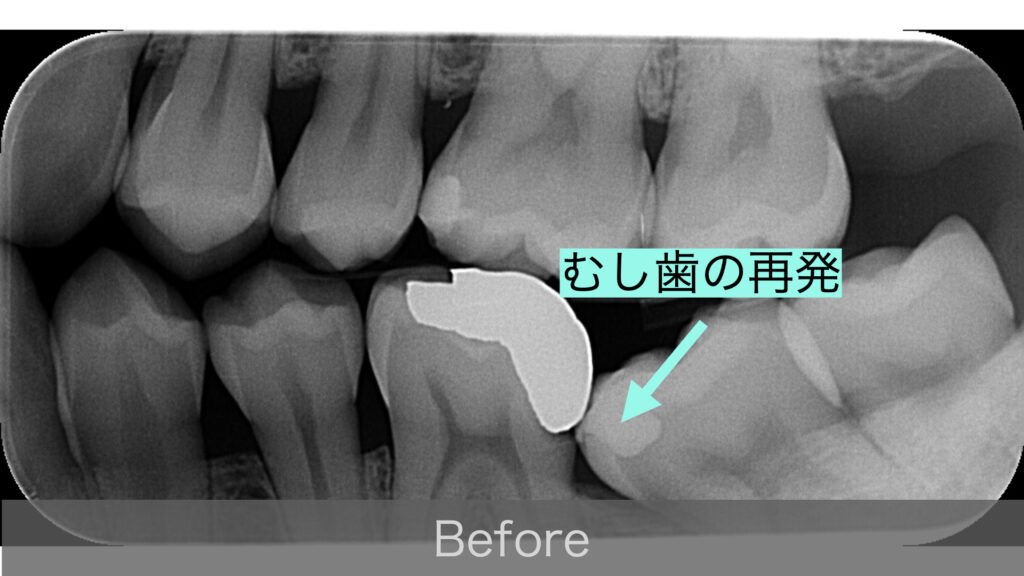

ある日の定期健診で、左下の奥歯(第1大臼歯)に入っていた金属の詰め物(インレー)の下で、むし歯が再発していることが分かりました。

ところが、問題がひとつありました。そのすぐ後ろにある歯(第2大臼歯)が、手前に向かって倒れ込むように傾いていたのです。このままでは、むし歯のある歯に器具が届かず、適切な治療ができません。